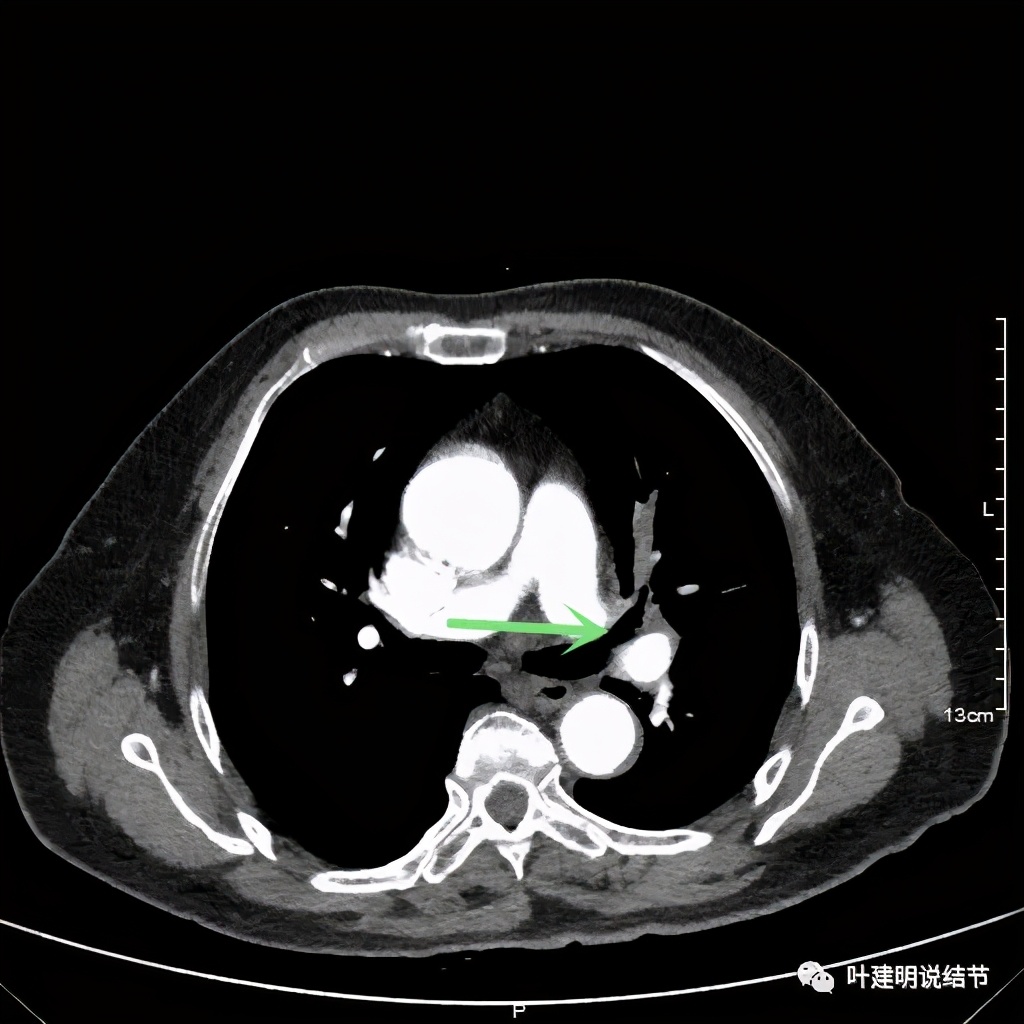

肺窗见原左上叶巨大占位已经明显缩小,甚至几乎不见了!而且上图示左上叶支气管清晰可见,内壁变光滑。纵隔窗增强又是如何的呢?

左上肺基本已经不见肿瘤,只在主动脉旁少许软组织影

上图示主动脉弓水平仍见软组织影